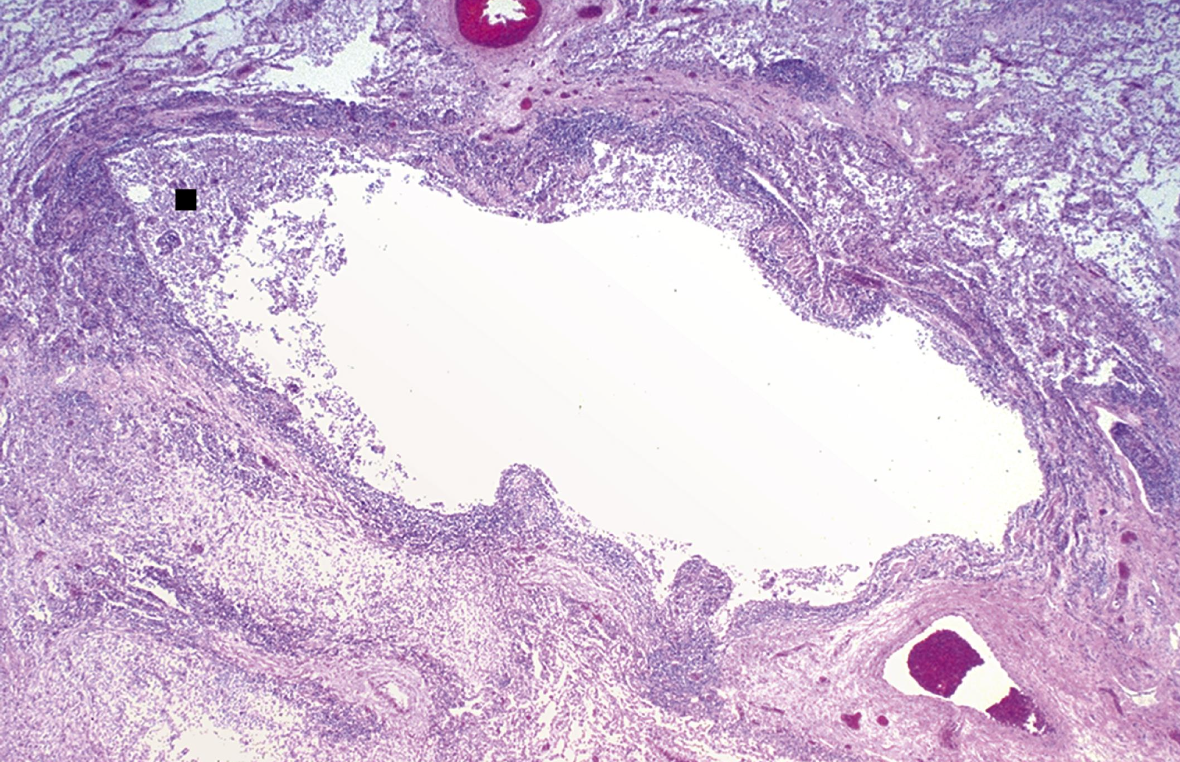

¿Qué es?

Bronquiectasias

Destrucción del músculo liso y tejido elástico deriva a infecciones persistentes y conduce a una dilatación permanente de los bronquios y bronquiolos

¿Cómo se ve morfológicamente las bronquiectasias?

Vias aéreas dilatadas de aspecto quístico llenos de secreción purulenta, afectación bilateral

Bronquiectasia Activa microscópicamente

Esfacelación del epitelio y zonas ulceradas con necrosis

Formación de abcesos

Pseudoestratificación o metaplasia del epitelio residual

Bronquiectasias crónica

Fibrosis de la pared bronquial, que lleva a obliteración de los lúmenes